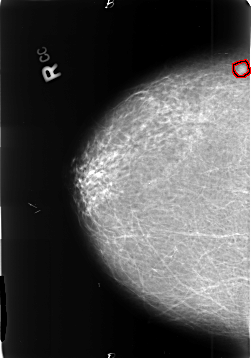

B_3402_1.RIGHT_MLO

RIGHT_CC LINES 4648 PIXELS_PER_LINE 3256 BITS_PER_PIXEL 12 RESOLUTION 50 OVERLAY

FILE: B_3402_1.RIGHT_CC.OVERLAY

TOTAL_ABNORMALITIES 1

ABNORMALITY 1

LESION_TYPE MASS SHAPE OVAL MARGINS ILL_DEFINED

ASSESSMENT 4

SUBTLETY 3

PATHOLOGY MALIGNANT

TOTAL_OUTLINES 1

BOUNDARY